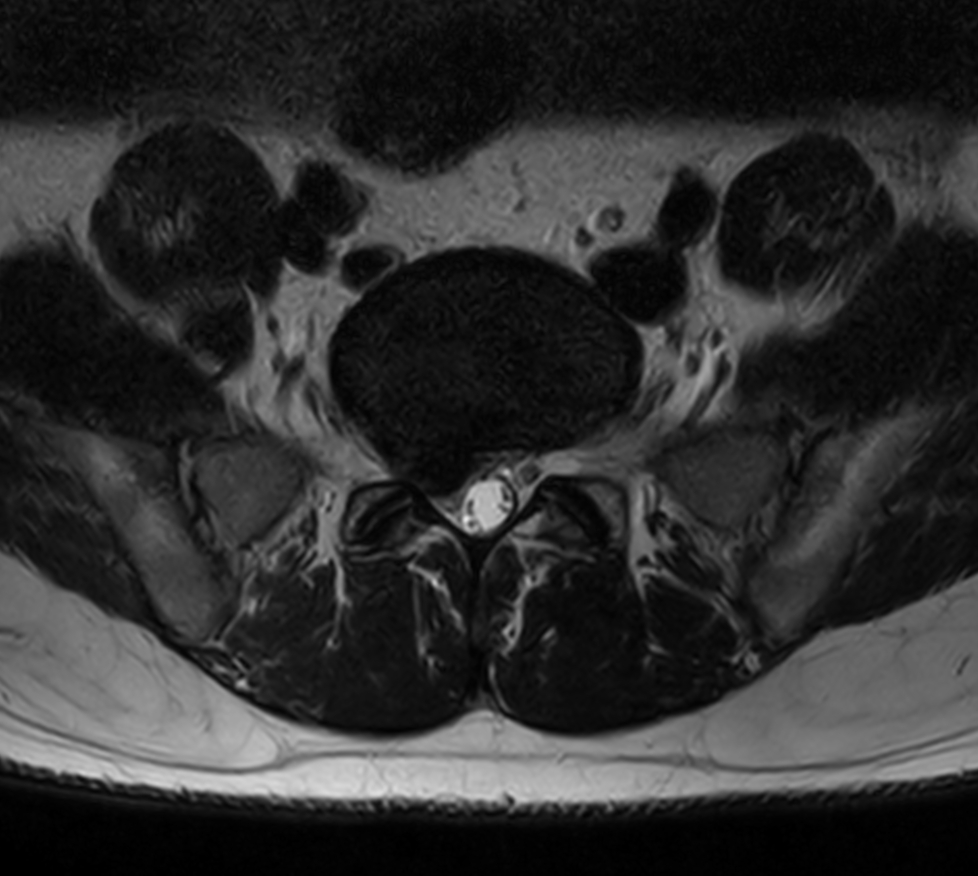

Lower back ache radiating to right lower limb. Diagnosis: Degenerative lower lumbar spondylosis, L5-S1 Stenosis

Axial T2w TSE